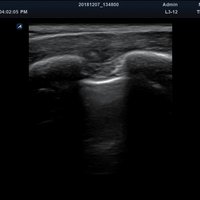

Das Alpinion minisono ist ein tragbares Hand-Ultraschallgerät, das eine sichere und schnelle Diagnostik u. a. in den Anwendungsbereichen Abdomen, MSK, Vaskulär, kleine Organe sowie Bauch und Brust bietet. An das minisono kann über USB-Kabel entweder eine Linear-Sonde oder eine Konvex-Sonde angeschlossen werden. Die komplette ultraschallspezifische Hardware ist in den Griffstücken integriert.

Anwendungsbereiche Abdomen MSK, Nerven, Karotis, periphere Gefäße, Schilddrüse, Mamma

Bildgebungs-Modi B-Modus, CF, M, PW, PD B-Modus, CF, M, PW, PD

• Speckle Reduction Imaging: Basisfilter zur Verbesserung der Bildqualität

• Advanced Speckle Reduction Imaging: Filtertechnologie zur Minimierung der Artefakte und Verbesserung der Definition der Gewebegrenzen